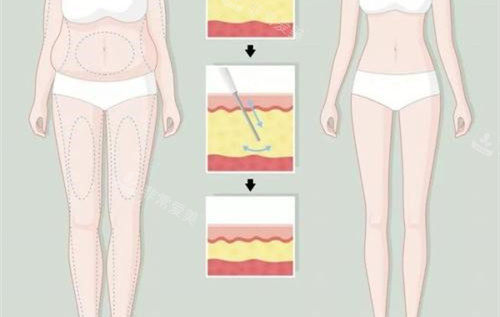

主治医生金院长在面诊时,用3D扫描技术生成了我腿部的三维模型,在屏幕上模拟出不同吸脂量对应的腿型变化,比较终确定右侧大腿抽取300ml、左侧280ml脂肪,小腿部分采用光纤溶脂技术。

金院长在设计方案时强调"保留1.5cm脂肪层"的原则,避免出现皮肤凹陷。

针对我膝盖内侧的脂肪堆积,他计划采用微小切口技术;而小腿部分则结合肌肉放松术,改善我长期穿高跟鞋导致的肌肉紧张。

护士先为我进行术前消毒,在腿部标记出吸脂区域。